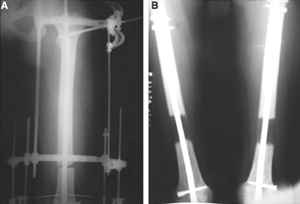

Вчера перешли с аппаратов на стежни с аб покрытием на правом бедре и левой голени.

На левом бедре оставили аппарат бедро-голень.

Как вы думаете если сделать следующее.

После заживления раны на левом бедре. Выполнить открытую реподицию и синтез пластиной для дистального бедра. Пластину в проксимальном направлении зафиксировать монокортикально.

А затем выпонить остеотомию бедра в верхней трети.

И тракцию бедра на стержне. Типа (СМ картинки).

После выращивания регенерата стержень блокировать.